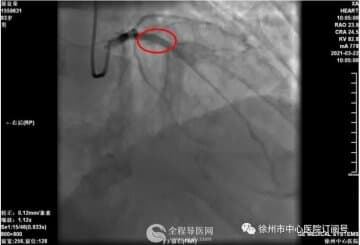

这是一名5年来反复晕厥8次的70岁男性患者,曾因晕厥摔伤,严重影响生活质量,多次住院行多种检查亦未能查明原因。此次入院后经徐医附院心内二科医师充分评估后一致认为运用常规检查手段很难明确诊断,植入式Holter可以最大限度地明确晕厥的性质和原因。在完善相关检查并排除手术禁忌后,徐医附院心内二科夏勇主任亲自为患者安装了第四代植入式Holter,局麻下,在患者左胸切开2厘米的小切口,做好相应囊袋将心电记录器置入皮下后缝合。手术时间约10分钟。手术操作简单、创伤小,患者几乎感觉不到痛苦。植入式Holter除患者根据症状主动触发记录器记录外,心电记录器本身也能根据其感知的心电事件及时自动触发记录器记录,尤其适用于发作时症状不明显或意识丧失以及行动不能自理的患者。对不明原因晕厥的病因诊断率最高,该项技术的开展将显著提高晕厥的诊疗水平。